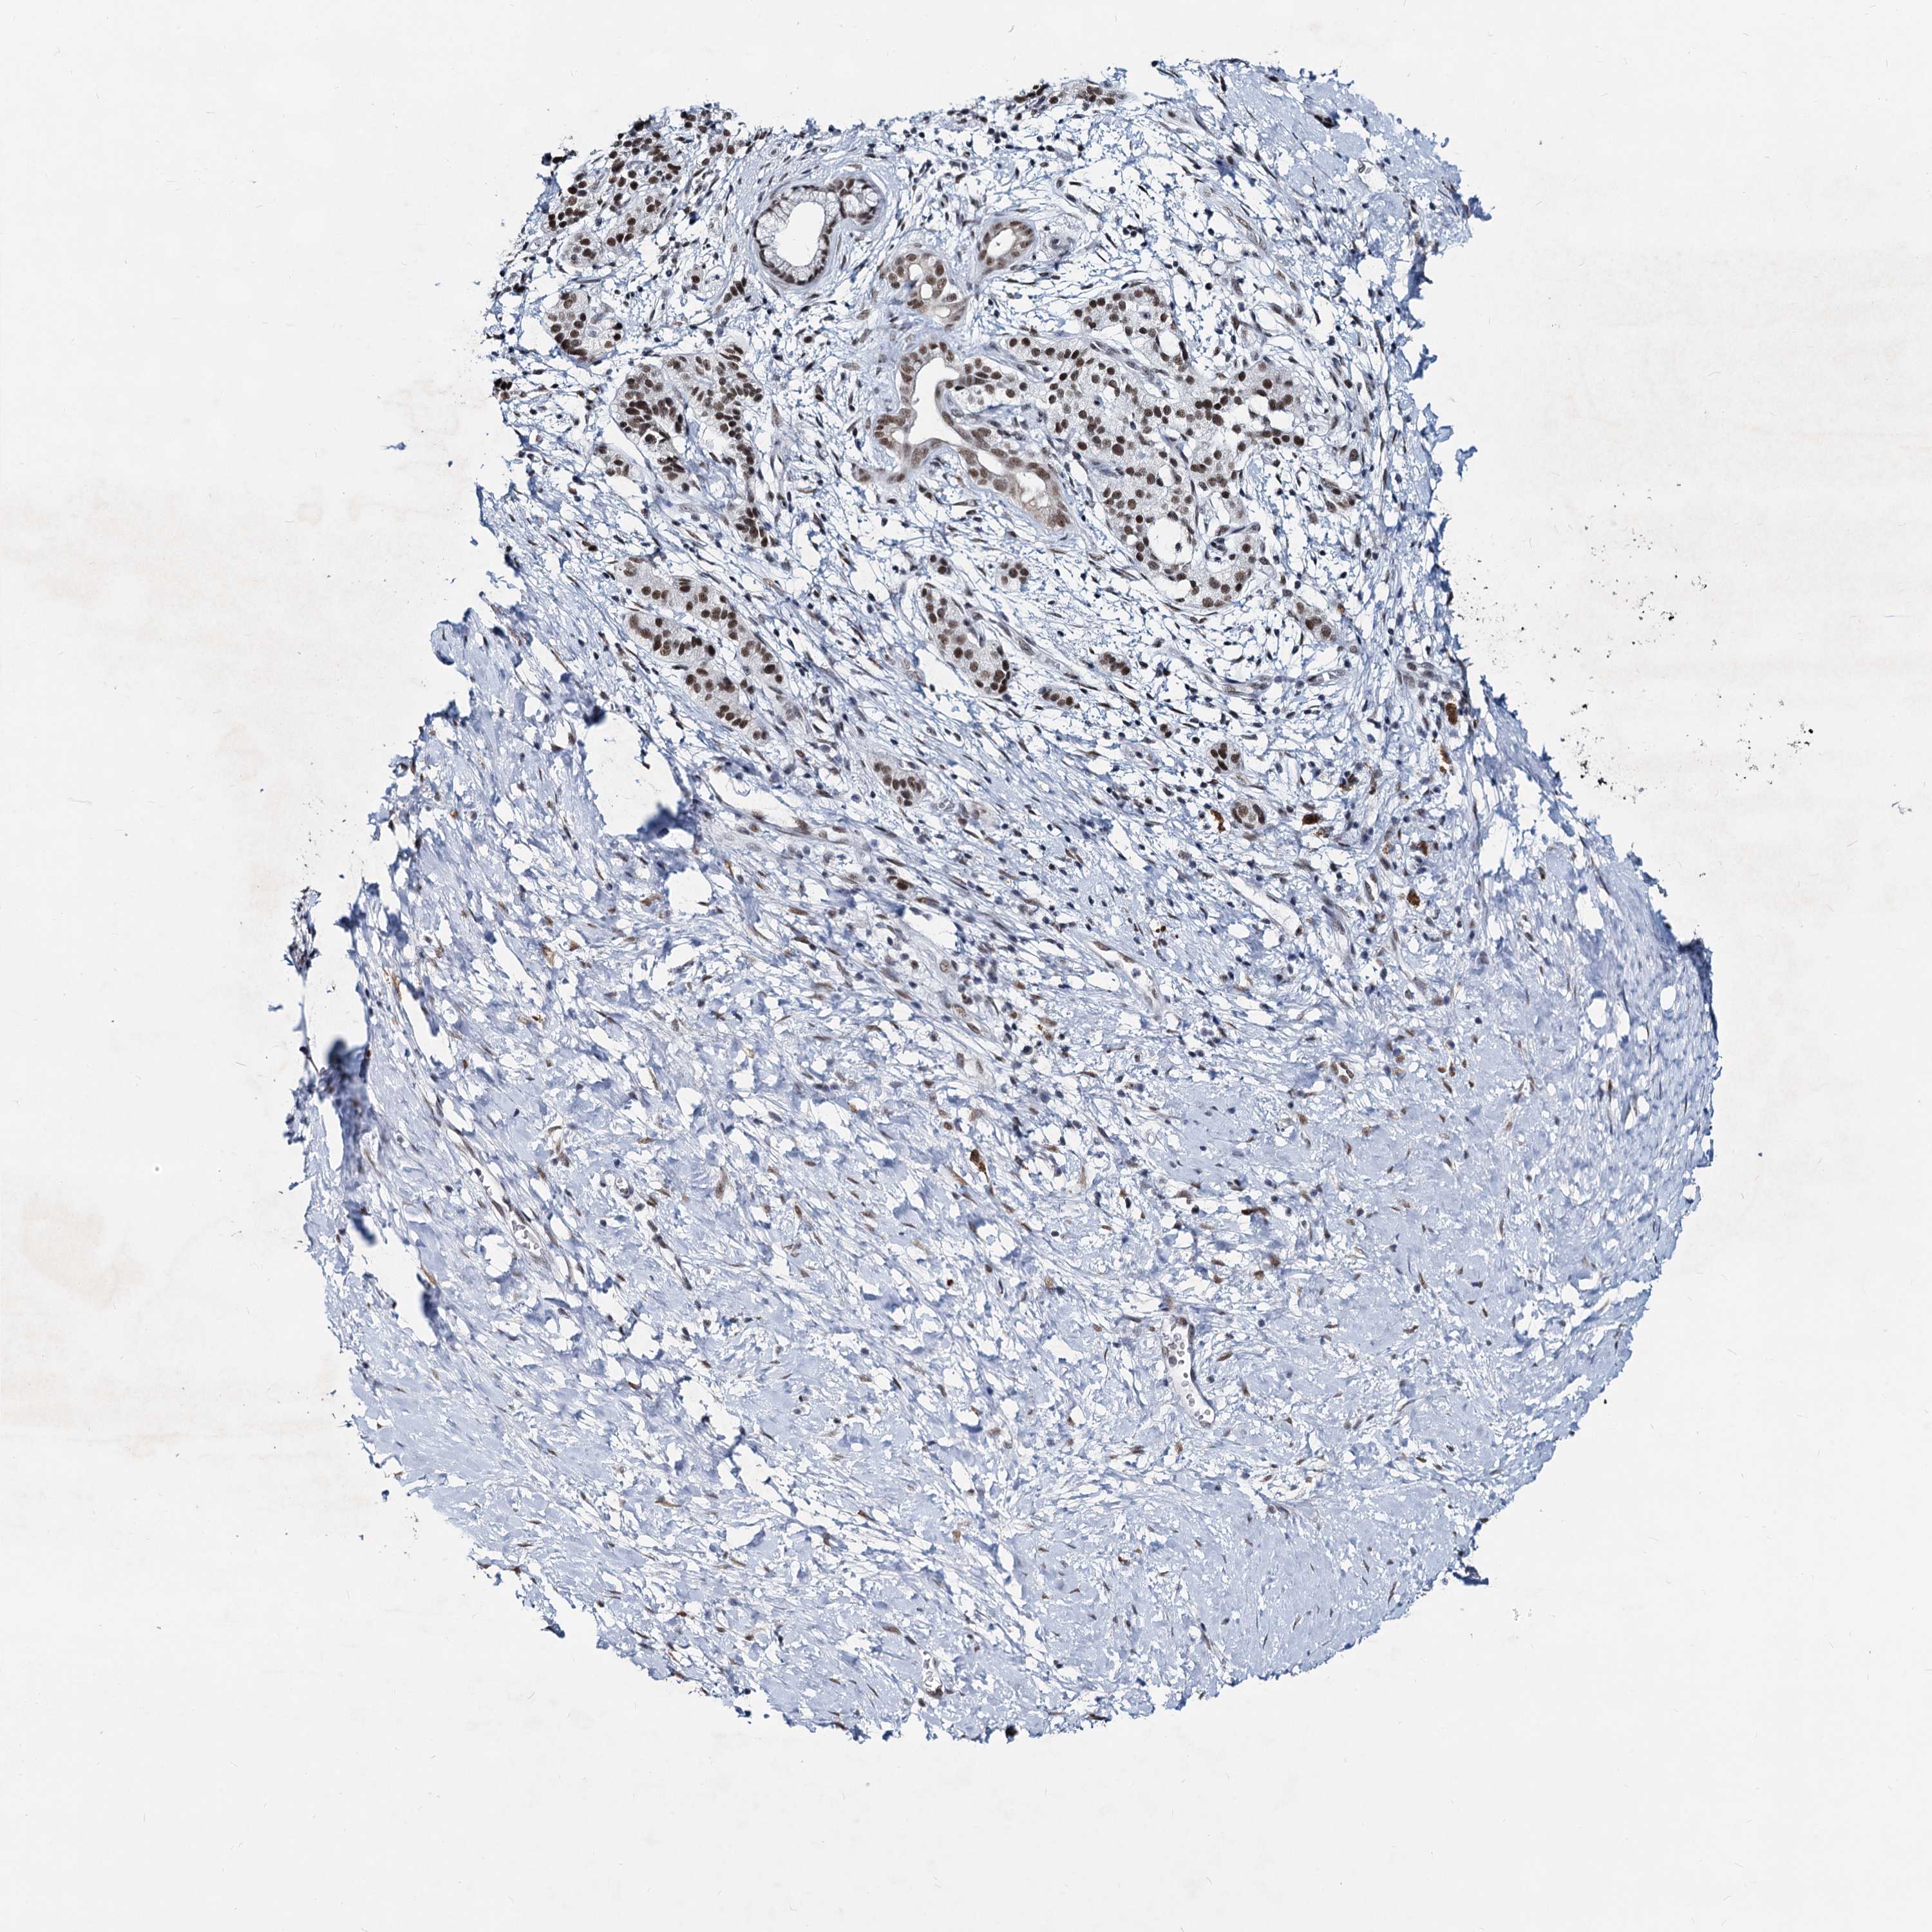

PANCREATIC CANCER - Protein expressioni

A mouse-over function shows sample information and annotation data. Click on an image to view it in a full screen mode. Samples can be filtered based on level of antibody staining by selecting one or several of the following categories: high, medium, low and not detected. The assay and annotation is described here.

Note that samples used for immunohistochemistry by the Human Protein Atlas do not correspond to samples in the TCGA dataset.

Antibody stainingi

Antibody staining in the annotated cell types in the current human tissue is reported as not detected, low, medium, or high, based on conventional immunohistochemistry profiling in selected tissues. This score is based on the combination of the staining intensity and fraction of stained cells.

Each image is clickable and will lead to virtual microscopy that enables deeper exploration of all samples and also displays staining intensity scores, fraction scores and subcellular localization as well as patient and tissue information for each sample.

Antibody HPA038002

Staining

High

Medium

Low

Not detected

Intensity

Strong

Moderate

Weak

Negative

Quantity

>75%

75%-25%

<25%

None

Location

Nuclear

Cytoplasmic/membranous

Cytoplasmic/membranous,nuclear

Adenocarcinoma, NOS